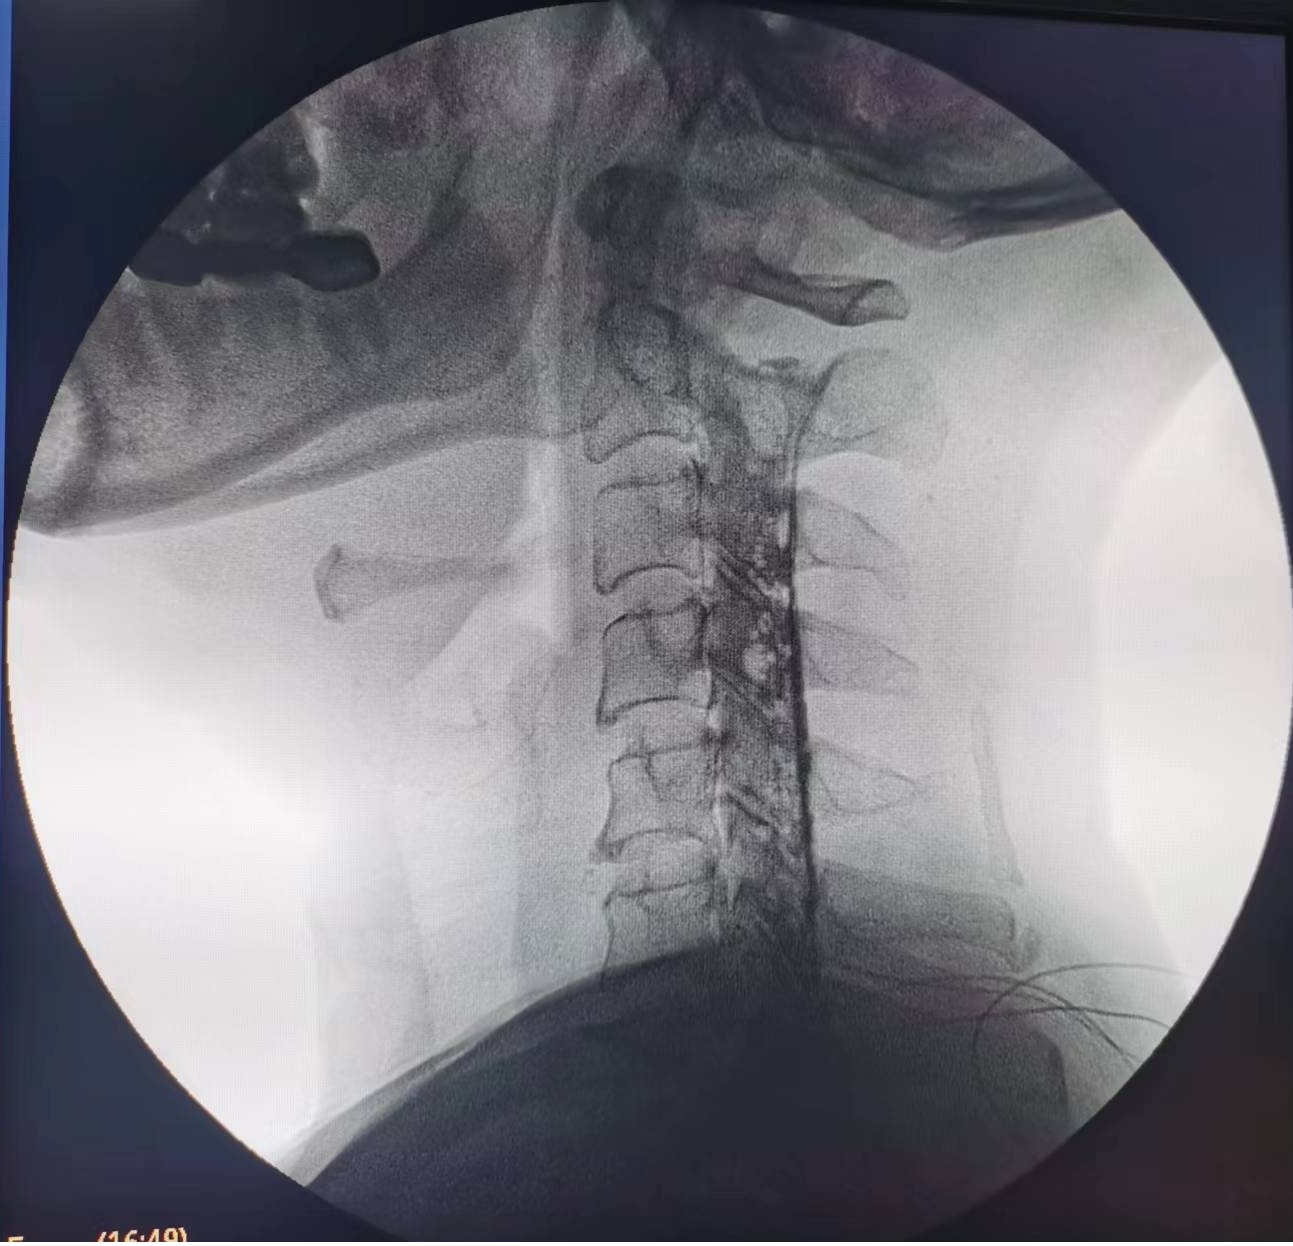

輾轉(zhuǎn)來到瀘州市中醫(yī)醫(yī)院疼痛科治療。由于疼痛嚴重,外加嚴重缺乏睡眠,黃大伯入院時焦慮、精神狀態(tài)很差??粗鼻邢虢獬纯嗟难凵瘢弁纯漆t(yī)生團隊抓緊時間完善診查,發(fā)現(xiàn)黃大伯病情為第6、7節(jié)頸椎間盤突出重,壓迫左側(cè)第7頸神經(jīng)根導致。考慮他年齡較大,團隊決定給他做一種微創(chuàng)手術——膠原酶化學溶解術:通過一支細小的針穿刺到突出的椎間盤,注射膠原酶,將突出的椎間盤溶解掉,以減除神經(jīng)的壓迫。

手術之后3天,黃大伯疼痛得到很好緩解,露出了許久沒有的笑容,終于可以安心躺著睡覺了,1個月后基本恢復了正常生活,6個月后復查CT發(fā)現(xiàn)突出的頸椎間盤已經(jīng)基本消失了,黃大伯一家人對治療效果非常滿意。

手術之前CT,巨大突出物 術后6個月復查CT:突出物消失